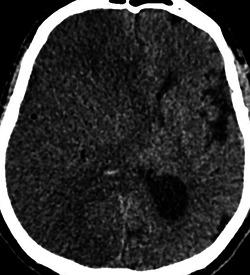

Of 5022 consecutive patients with AIS, 870 underwent EVT. Seven patients (0.8%) had EVT following cardiac surgery. Operations varied: two coronary artery bypass grafting (CABG), two transcatheter AVR, one redo surgical aortic valve replacement (AVR), one mitral valve repair and one patient with combined aortic and mitral valve replacements and CABG. Meantime postsurgery to stroke symptoms onset was 3 days (range 0-9 days). Median NIHSS was 26 (range 10-32). Five patients had middle cerebral artery occlusion and two internal carotid artery (n = 2). Median time between onset of symptoms and recanalization was 157 min (range 97-263). Two patients received Intra-arterial Thrombolysis. All patients survived and were discharged to another hospital (n = 3), home (n = 2), or rehabilitation facility (n = 2). Median 3-month mRS was 3 (range 0-6).

在 5022 例连续 AIS 患者中,870 例行 EVT。7 例(0.8%)在心脏手术后行 EVT。手术类型多样:2 例冠状动脉旁路移植术(CABG)、2 例经导管主动脉瓣置换术(AVR)、1 例再次外科主动脉瓣置换术(AVR)、1 例二尖瓣修复术和 1 例主动脉瓣和二尖瓣置换术联合 CABG。同时,术后至卒中症状发作时间为 3 天(范围 0-9 天)。NIHSS 中位数为 26(范围 10-32)。5 例患者大脑中动脉闭塞,2 例颈内动脉闭塞(n=2)。症状发作至再通的中位时间为 157 分钟(范围 97-263)。2 例患者接受了动脉内溶栓治疗。所有患者均存活并出院至另一家医院(n=3)、家中(n=2)或康复设施(n=2)。中位 3 个月 mRS 为 3(范围 0-6)。